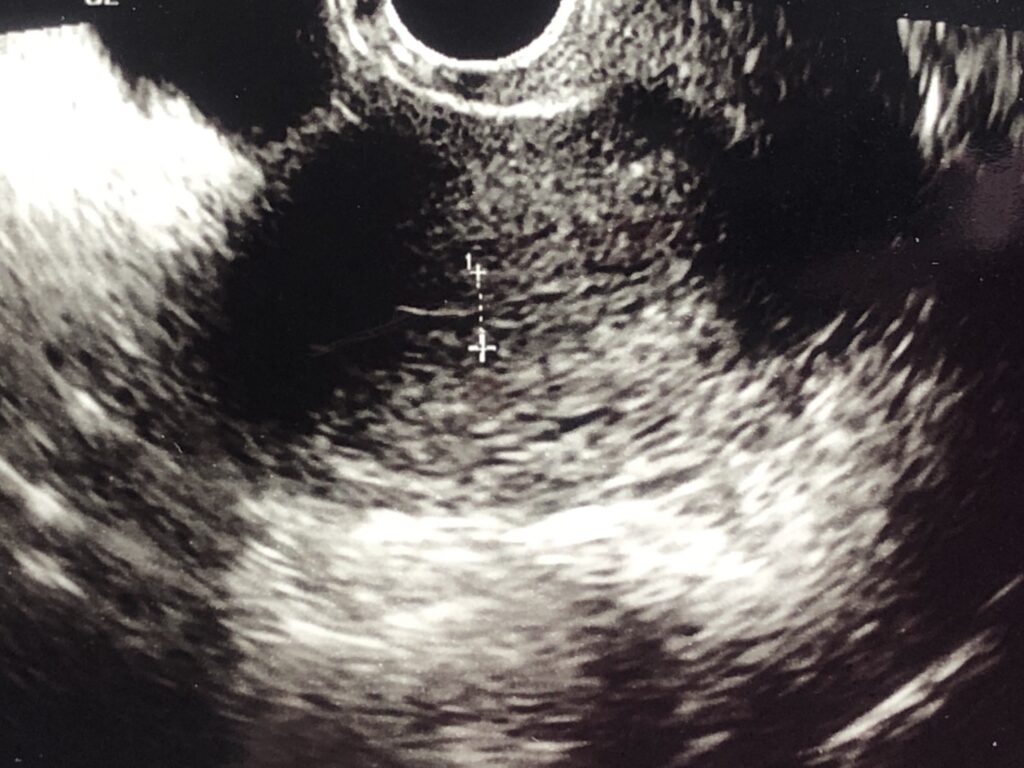

D11~13内膜・卵胞チェック

内膜・卵胞の育ち具合を確認しながら、人工授精(AIH)の日付を決めていきます。

スムーズに行けば1回で済みますが、育ちが悪いと通院回数が増えることも。。

D13に卵胞チェック、D14に人工授精(AIH)が私の流れでした。

●排卵の目安

・内膜:10mmあるとふかふかベッド

・卵胞:20mmあたりが排卵する目安

内膜・卵胞のチェックでも見極められない場合は、尿検査でホルモン値(LHサージ)を確認します。

私は毎回尿検査でも分からず(無色)、採血までして日にちを決めていました。

人工授精(AIH)の翌日や、翌開院日にエコーで排卵しているかの確認。